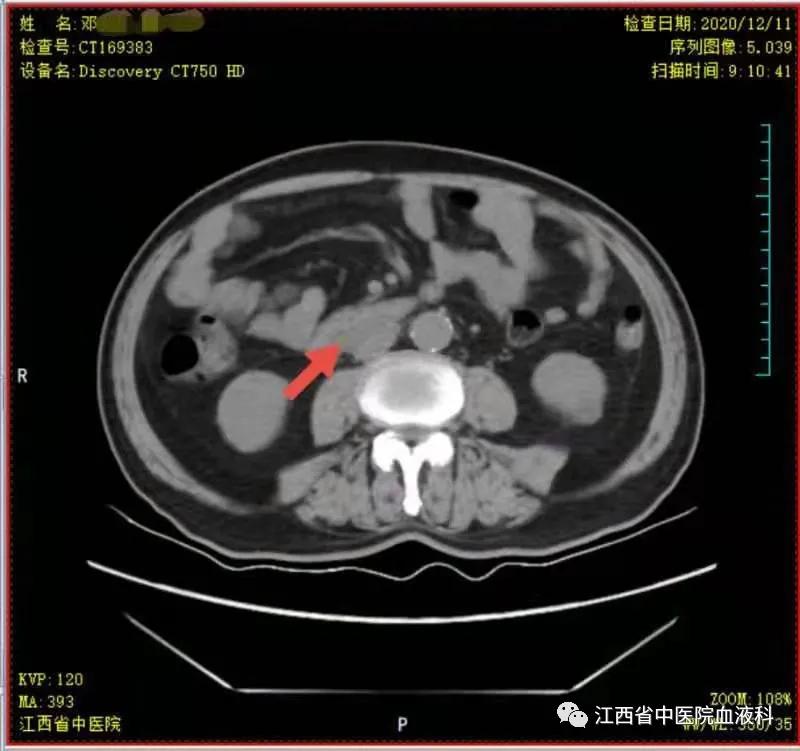

2020年10月中旬邓大爷在家人的陪同下来我科就诊,全腹部增强CT提示:右侧*丸睾**切除术后复查:1.腹膜后(胰头后下方)、双侧肾上腺区团块状异常强化影。2.肝左内叶上段小囊肿,双肾小囊肿,较前相仿。3.右侧腹股沟前方、皮下条索、小片影,境界不清,较前减小,拟为术后改变。4.右下腹腔少许钙化淋巴结,较前相仿。因病情危急,考虑邓大爷高龄、体能差、窦性心动过缓(平均心率50次/分)心脏功能差等情况,经讨论于2020-10-24起第一次行减剂量方案R-miniCHOP(利妥昔单抗700mg d0、环磷酰胺700mg d1、多柔比星40mg d1、长春瑞滨20mg d1、地塞米松10mg d1-5)方案。第一次化疗后评估病情,腹腔瘤体缩小了2/3,取得了很好的治疗效果,可邓大爷心脏却亮起了红灯,经过了积极护心等支持治疗后,大爷心脏功能有所恢复。遂于2020-11-19、2020-12-10行2次R-miniCOP方案(去除了具有心*毒脏**性的多柔比星),三次化疗结束后予评估病情,提示腹腔包块明显缩小,淋巴瘤病情有所好转(见图1至4)。

图2 第一次化疗后瘤块